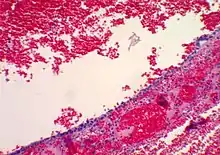

| Corpus luteum cyst with bleeding. Fresh blood is anechoic (black). A protrusion of coagulated blood (lighter in color) can also be seen in the top of the cyst. | |